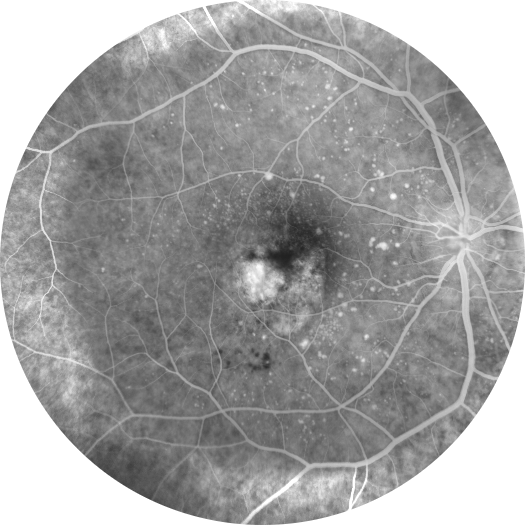

Her iki gözde doğuştan bu yana görme problemleri olan 11 yaşındaki erkek hastanı ...